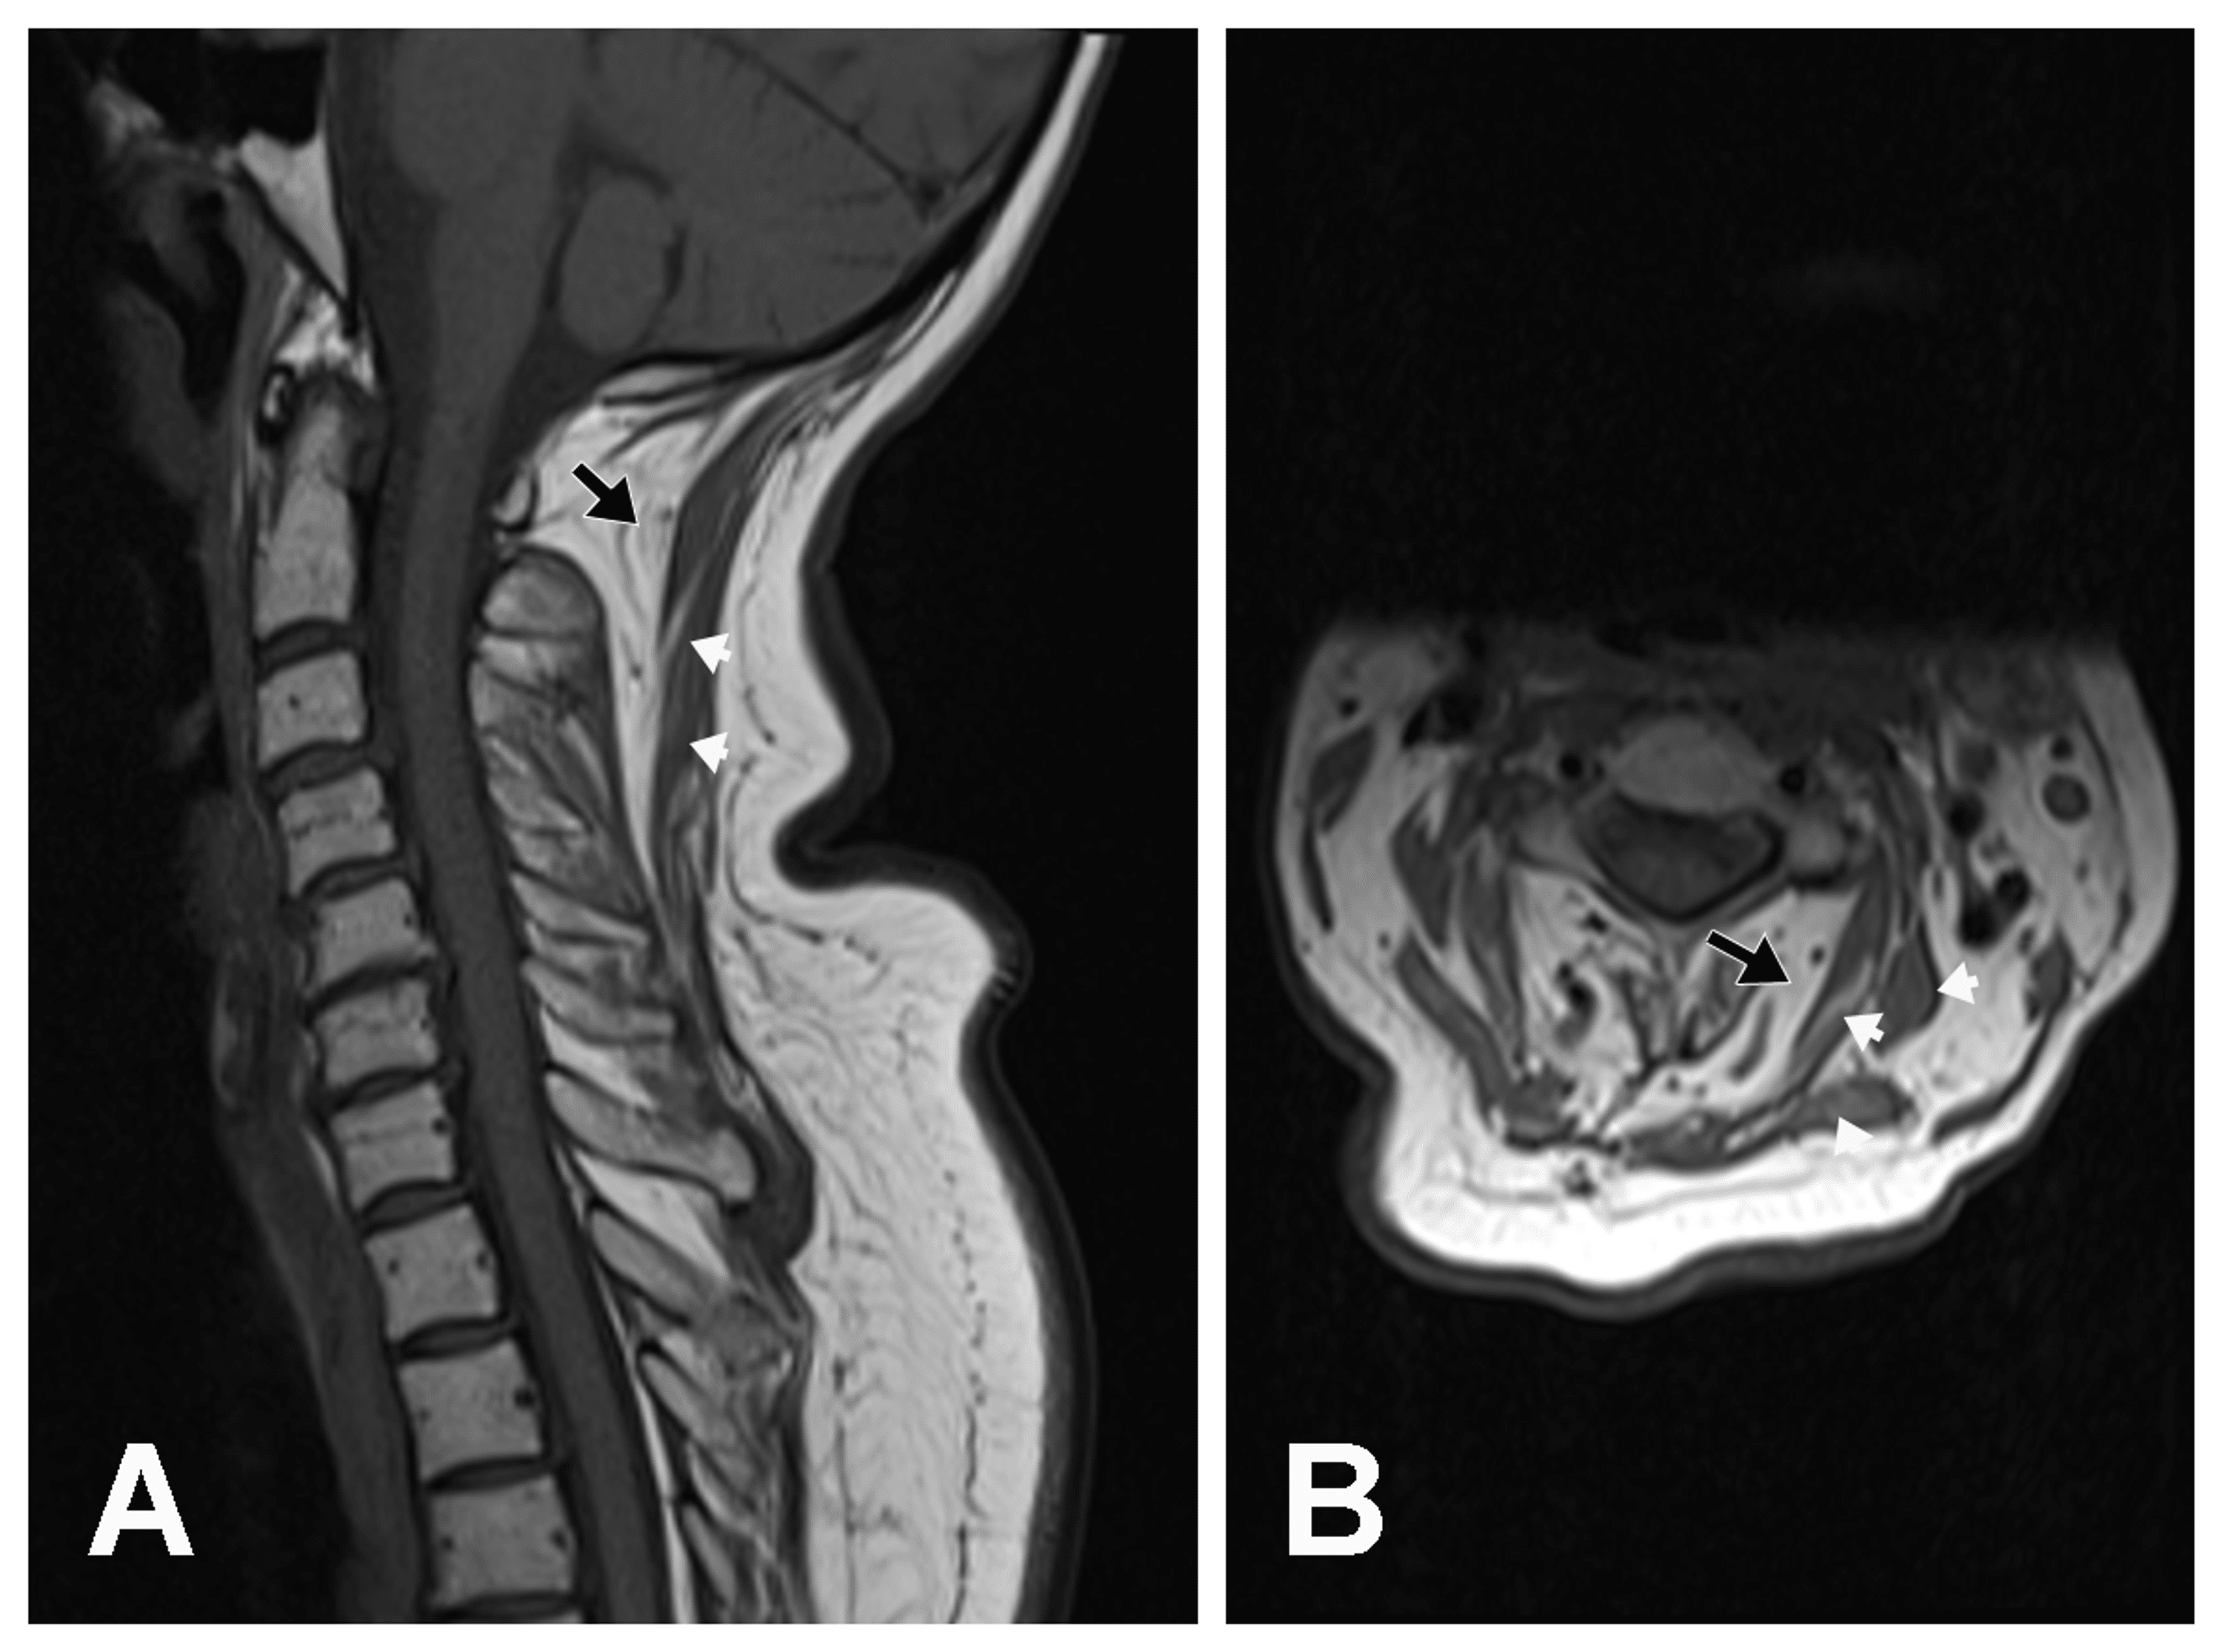

Dropped head syndrome as a presenting sign of scleromyositis Journal Neck Drop Head Syndrome Mris reveal that the affected muscles appear atrophic, edematous, and. Dropped head syndrome (dhs) is a rare condition characterized by severe weakness of neck extensors and may associate with weakness of shoulder girdle and proximal arm muscles. Neuromuscular causes are characterised by prominent neck extensor weakness, with minimal or absent neck flexor weakness. » dropped head syndrome is a group. Neck Drop Head Syndrome.

Dropped head syndrome due to myogenic atrophy a case report of Neck Drop Head Syndrome Neuromuscular causes are characterised by prominent neck extensor weakness, with minimal or absent neck flexor weakness. Dropped head syndrome (dhs) is known as a “chin on chest” deformity. It is a rare condition that is due to the gradual weakening of the muscles in the back of the neck, called “neck extensors”. » dropped head syndrome is a group of. Neck Drop Head Syndrome.